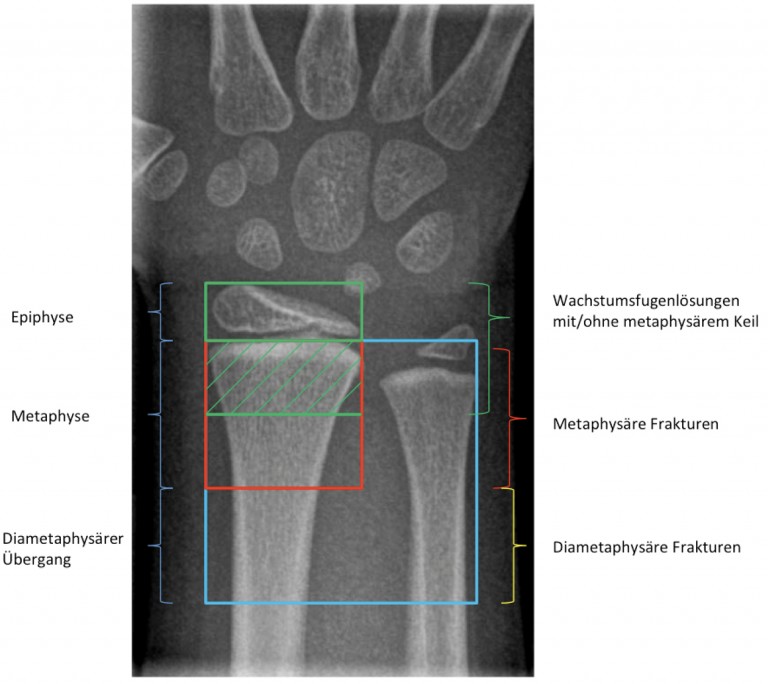

Source: ulaccampoc.pages.dev CMEArtikel Distale Radiusfrakturen im Kindesalter Sinn und Unsinn in der , Folgen einer Radiusfraktur: von Bewegungseinschränkungen bis chronischen Schmerzen Komplikationen nach distalen Radius-frakturen können eine Folge der Verlet-zung selbst oder der Behandlung sein und werden nach dem Schweregrad in „Minor"- und „Major"-Komplikationen mit und ohne Notwendigkeit einer chi-rurgischen Intervention unterteilt